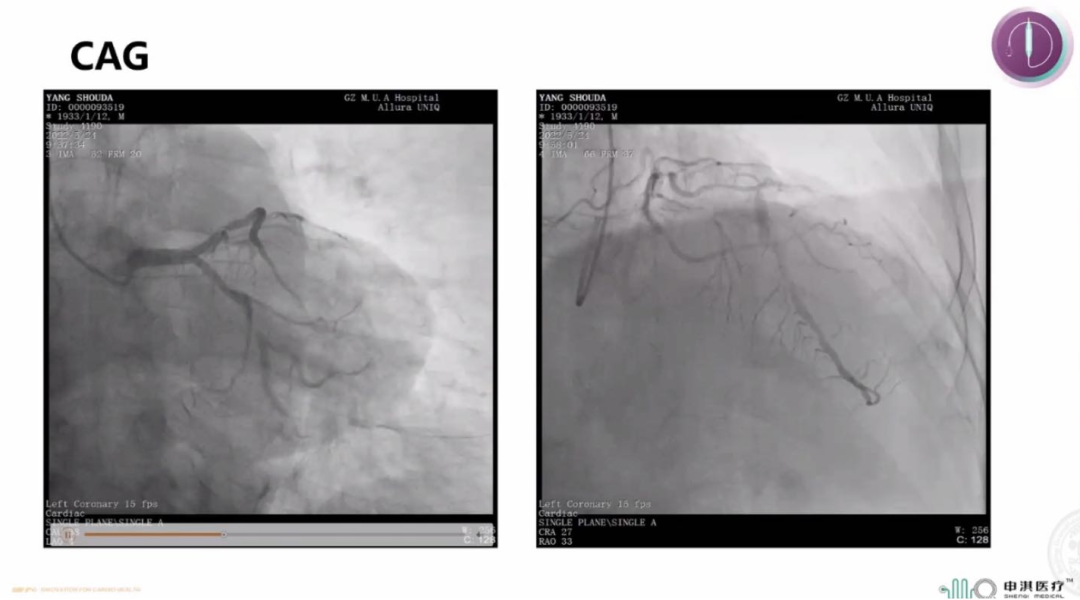

该患者为90岁高龄男性,既往有PCI史,且合并糖尿病、高血压、慢性肾功能不全。冠脉造影示LCX支架内次全闭塞,合并重度钙化;LAD近中段弥漫狭窄。手术过程中首先对LAD行IVUS检查示MSA 3.45mm²,可见表浅的钙化斑块。ISR是DCB的IA类适应症,于是术者在进行充分预处理后首先使用申淇3.0*30mm DCB扩张LCX-ISR病变80s。LAD病变弥漫,且患者为高出血风险,于是同样选择申淇3.5*20mm DCB治疗LAD病变,手术即刻效果满意。

该患者术后1个月发生消化道出血,考虑到患者此前治疗选择的是DCB而非DES,且即刻手术效果理想,故暂时停用了双联抗血小板治疗,联合止血、抑酸等对症处理后消化道出血逐步控制,且并未发生冠脉事件。

这一病例提示着,即使是短至一个月的双抗疗程,DCB也依然表现出良好的安全性。